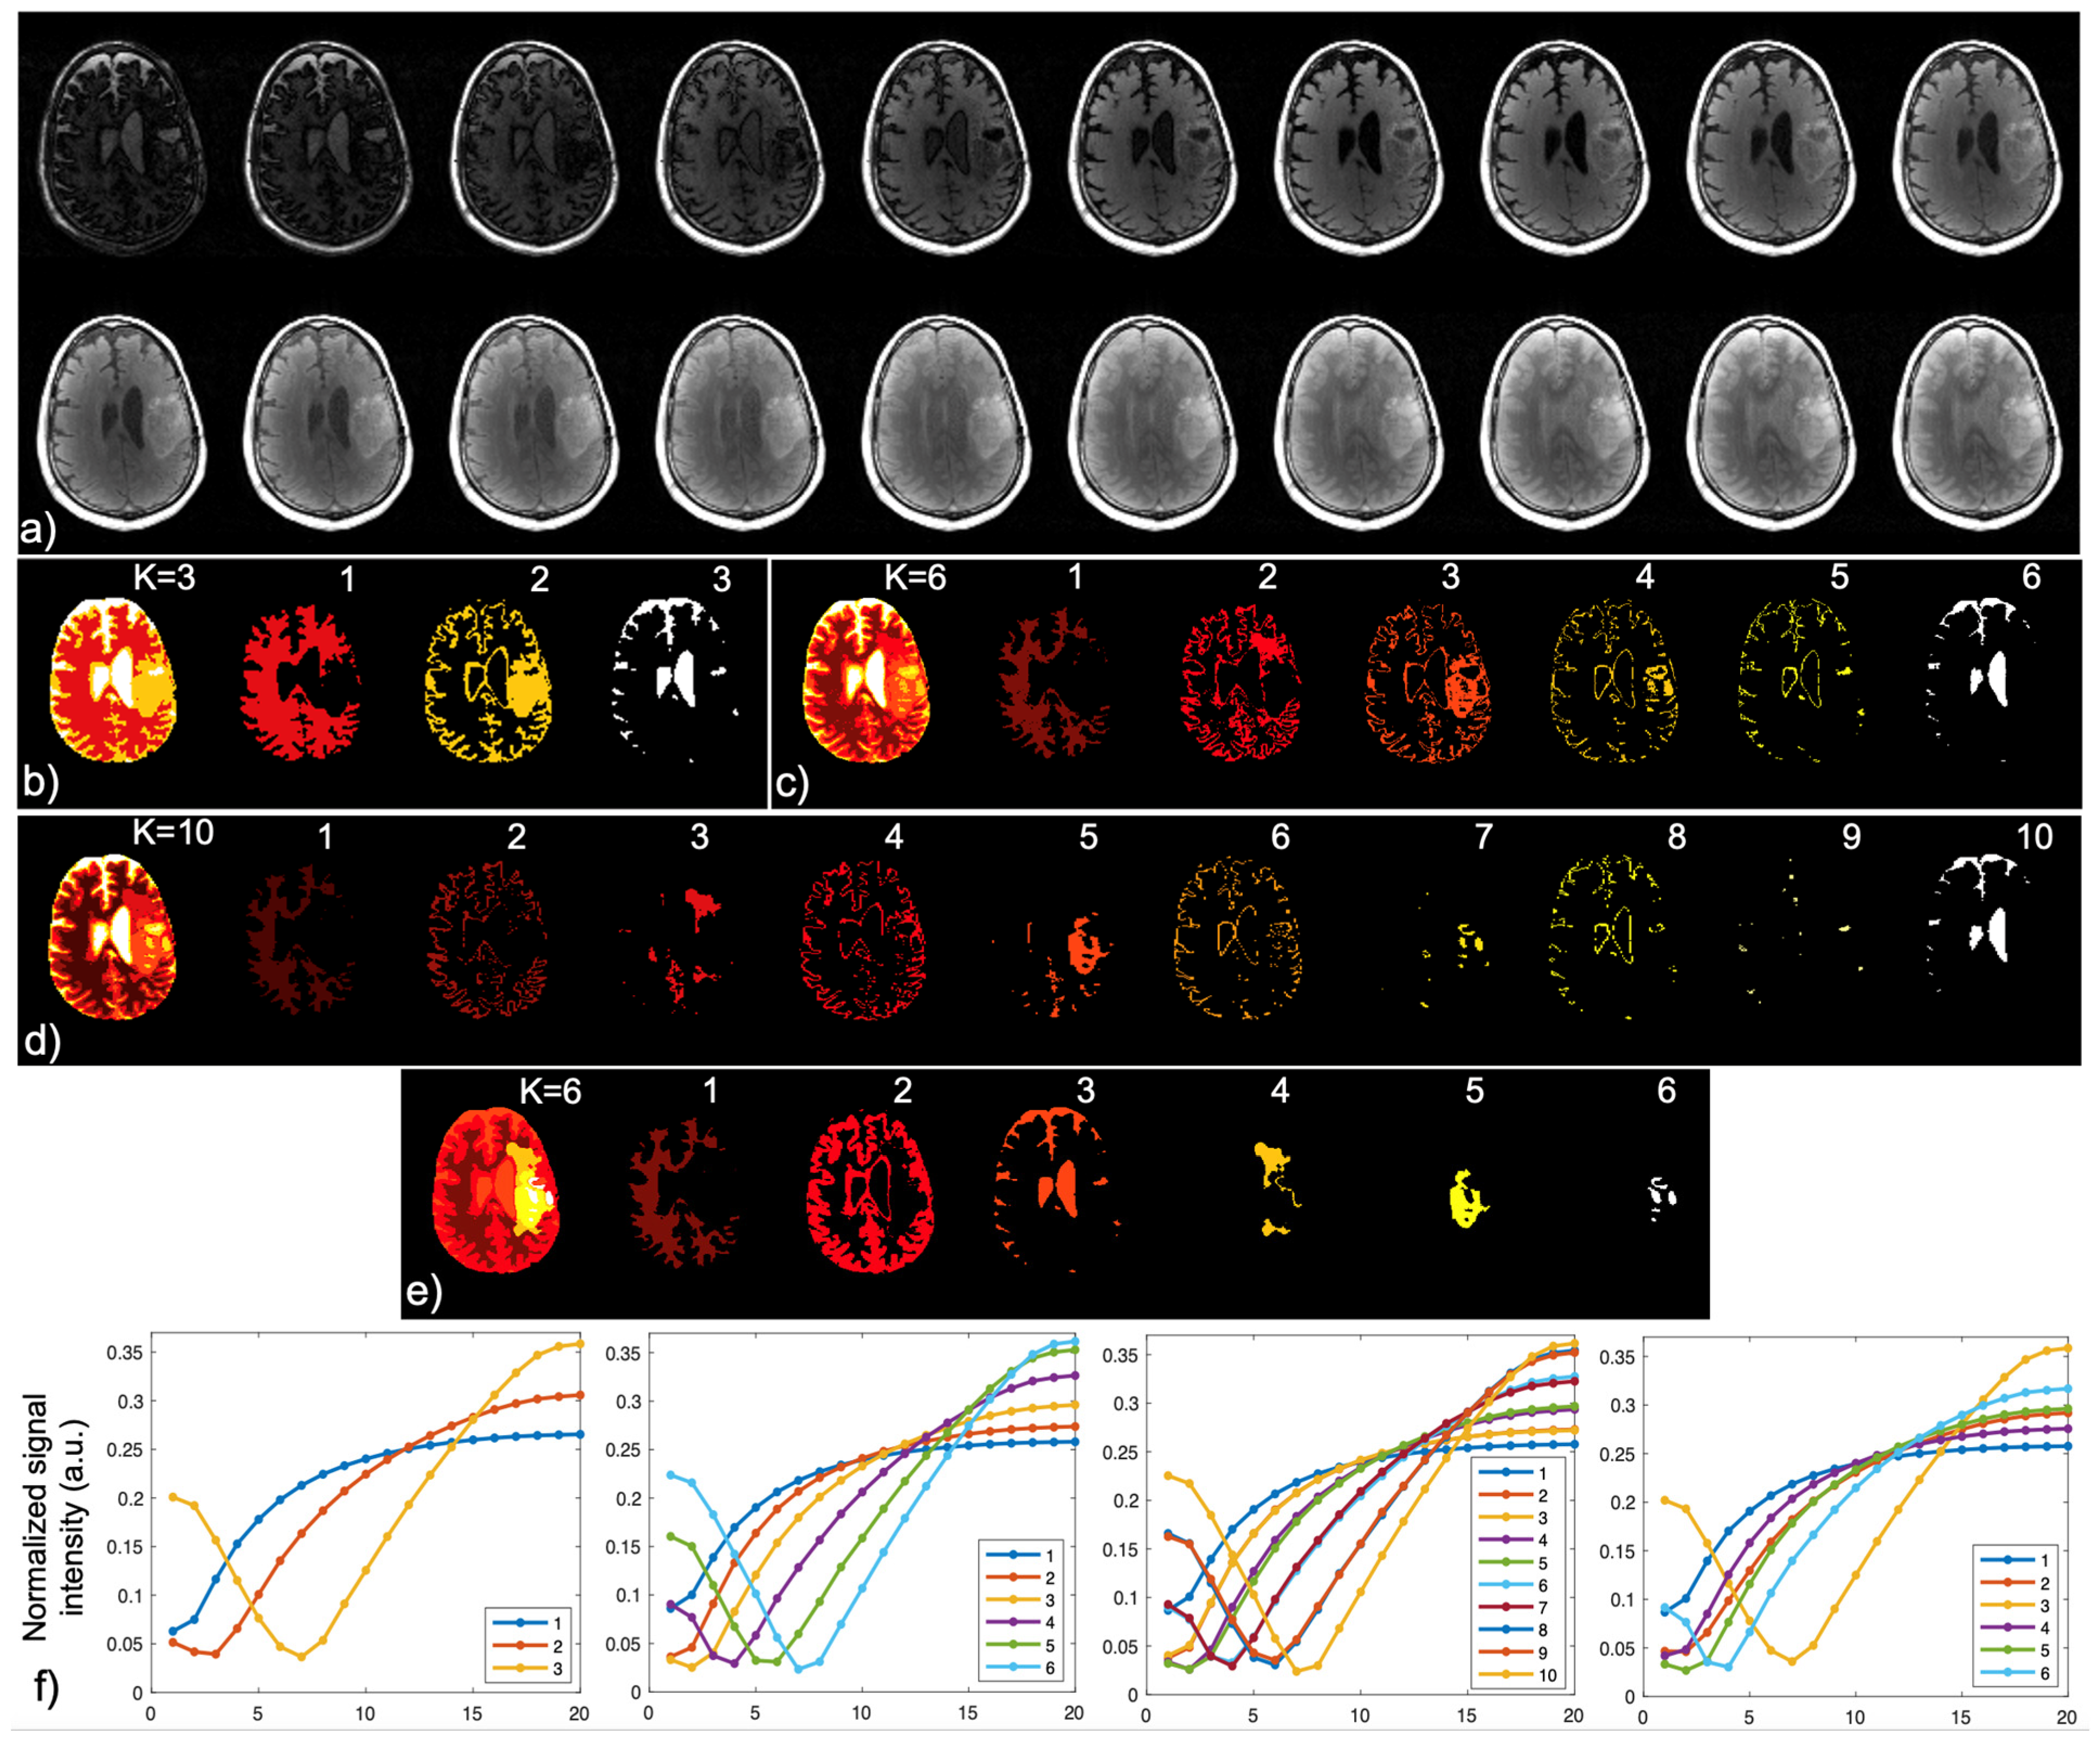

2.2. Optimization of Scan Parameters

2.3. Acceleration and Image Reconstruction

2.4. Brain Tissue and Lesion Segmentation

2.5. Two-Compartment Modeling and Multi-Parametric Mapping